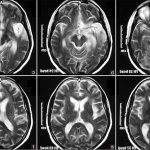

Внутренние кровотечения не просто распознать, особенно это касается его скрытой формы, которая не проявляет себя никакими специфическими признаками. Среди внутренних скрытых геморрагий чаще всего встречаются кровоизлияния в полость сустава, в желудочки мозга, в плевральную и брюшную полость.